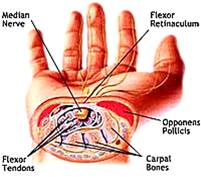

The Opponens Pollicis Muscle

The nerve passes under and through several arm muscles, through the carpal tunnel in your wrist, and finally a muscle of your thumb called the opponens pollicis muscle impinges on the nerve.

The nerve passes under and through several arm muscles, through the carpal tunnel in your wrist, and finally a muscle of your thumb called the opponens pollicis muscle impinges on the nerve.

The tight muscles entrap the median nerve, but they also put a strain on your wrist and hand. The analogy I use is pulling your hair and your scalp hurts. In the same way, the muscle pulls on the insertion points on your wrist and hand, and you feel pain.

The following treatment is for the muscle of your thumb, called “opponens pollicis.” This muscle pulls your thumb into the center of your palm.

An important factor is the muscle originates on the ligament that goes across the top of the carpal tunnel. When it gets tight it is pulling hard on the ligament and it presses down onto the median nerve. This causes your thumb and first two fingers to go numb.